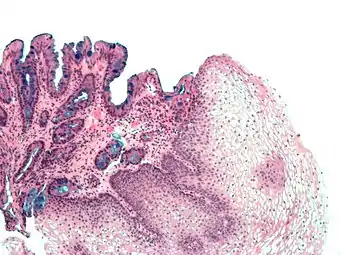

- [Micrograph] of normal stratified squamous epithelium and the metaplasic epithelium of Barrett's esophagus (left of image). Alcian blue stain.